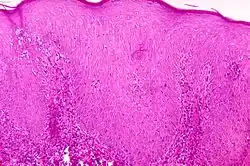

Pinta – choroba zakaźna zaliczana do krętkowic endemicznych zwanych też niewenerycznymi, wywołana przez krętka Treponema carateum (od tej nazwy bierze się również czasami spotykane określenie tej choroby – carate).

Pinta jest chorobą skóry, która rozpoczyna się zwykle od pojawienia się grudki zlokalizowanej w różnych częściach ciała. Grudka stopniowo się rozrasta, zlewając się z sąsiednimi. Po różnym okresie trwania, zmiany te stopniowo zaczynają się odbarwiać, powodując w końcu powstanie białych plam pozbawionych melaniny oraz powodując w tych miejscach zaniki naskórka.